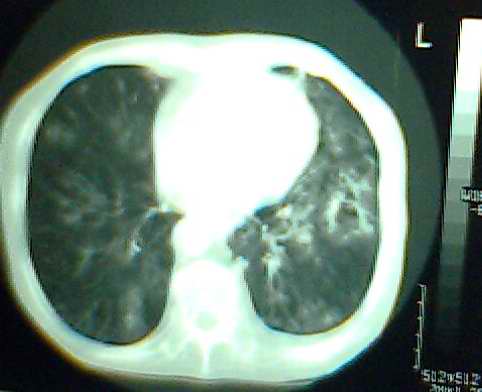

以上是2009-05-25的照片。

以下是引用hhx58在2009-9-11 19:48:00的发言:[br]有4个是心电监护的电极。[br]ct图片可见有肺气囊。但未拿到片上传。

以下是引用37度在2009-9-12 11:54:00的发言:[br][br] [br] 支气管扩张合并混合型感染 [br] [br]

以下是引用dyqct在2009-9-12 8:42:00的发言:[br]慢性支气管炎合并间质纤维化、肺气肿、支气管扩张、感染。建议ct进一步检查。

以下是引用黑白光影在2009-9-12 16:43:00的发言:[br]慢支并感染(霉菌?)